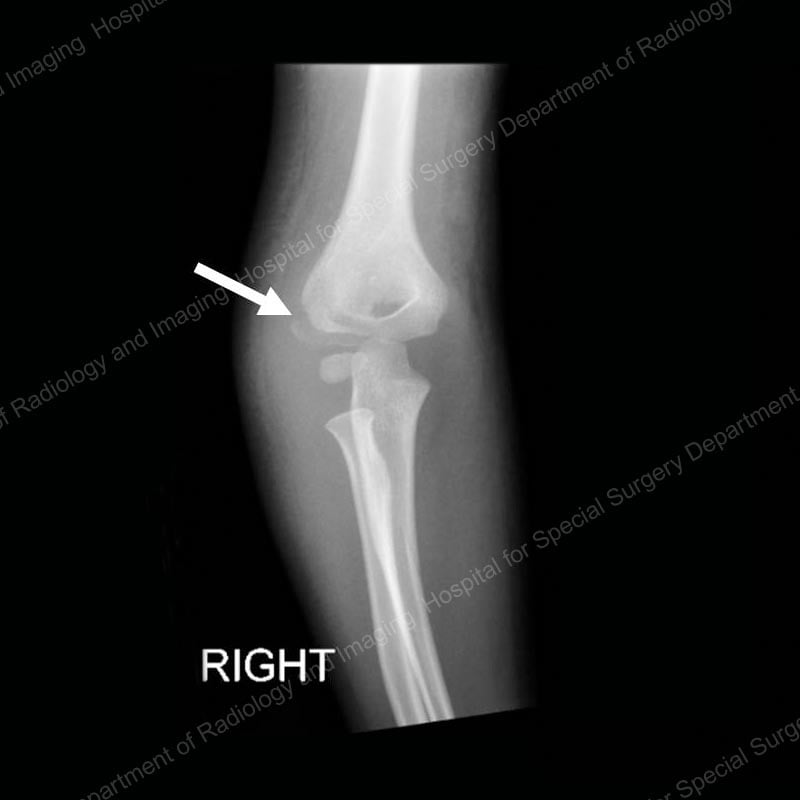

Lateral condyle fractures

These breaks occur at the outer part of the elbow, an area that serves as an attachment point for most of the muscles that straighten out the wrist and fingers, and also for the ligaments that stabilize the elbow joint. Lateral condyle fractures usually result from relatively low energy injuries, and the growth plate of the elbow typically resumes normal growth after the .

Figure 3: Anterior (front) X-ray view of a lateral condyle fracture prior to treatment. The arrow points to the fracture line.

Orthopedic surgeons classify these injuries based on the degree to which they are displaced and determine treatment accordingly. If the fracture is non-displaced, that is, the fracture line can be seen on an image, but the bone has not shifted out of position, the patient may only require immobilization of the arm in a splint or cast. However, if any displacement is found, the bone needs to be realigned and stabilized with pins or wires as in supracondylar fractures. (Please see Figure 2 for an example of this type of wiring.) This surgery may or may not require an incision, depending on the extent of the displacement.